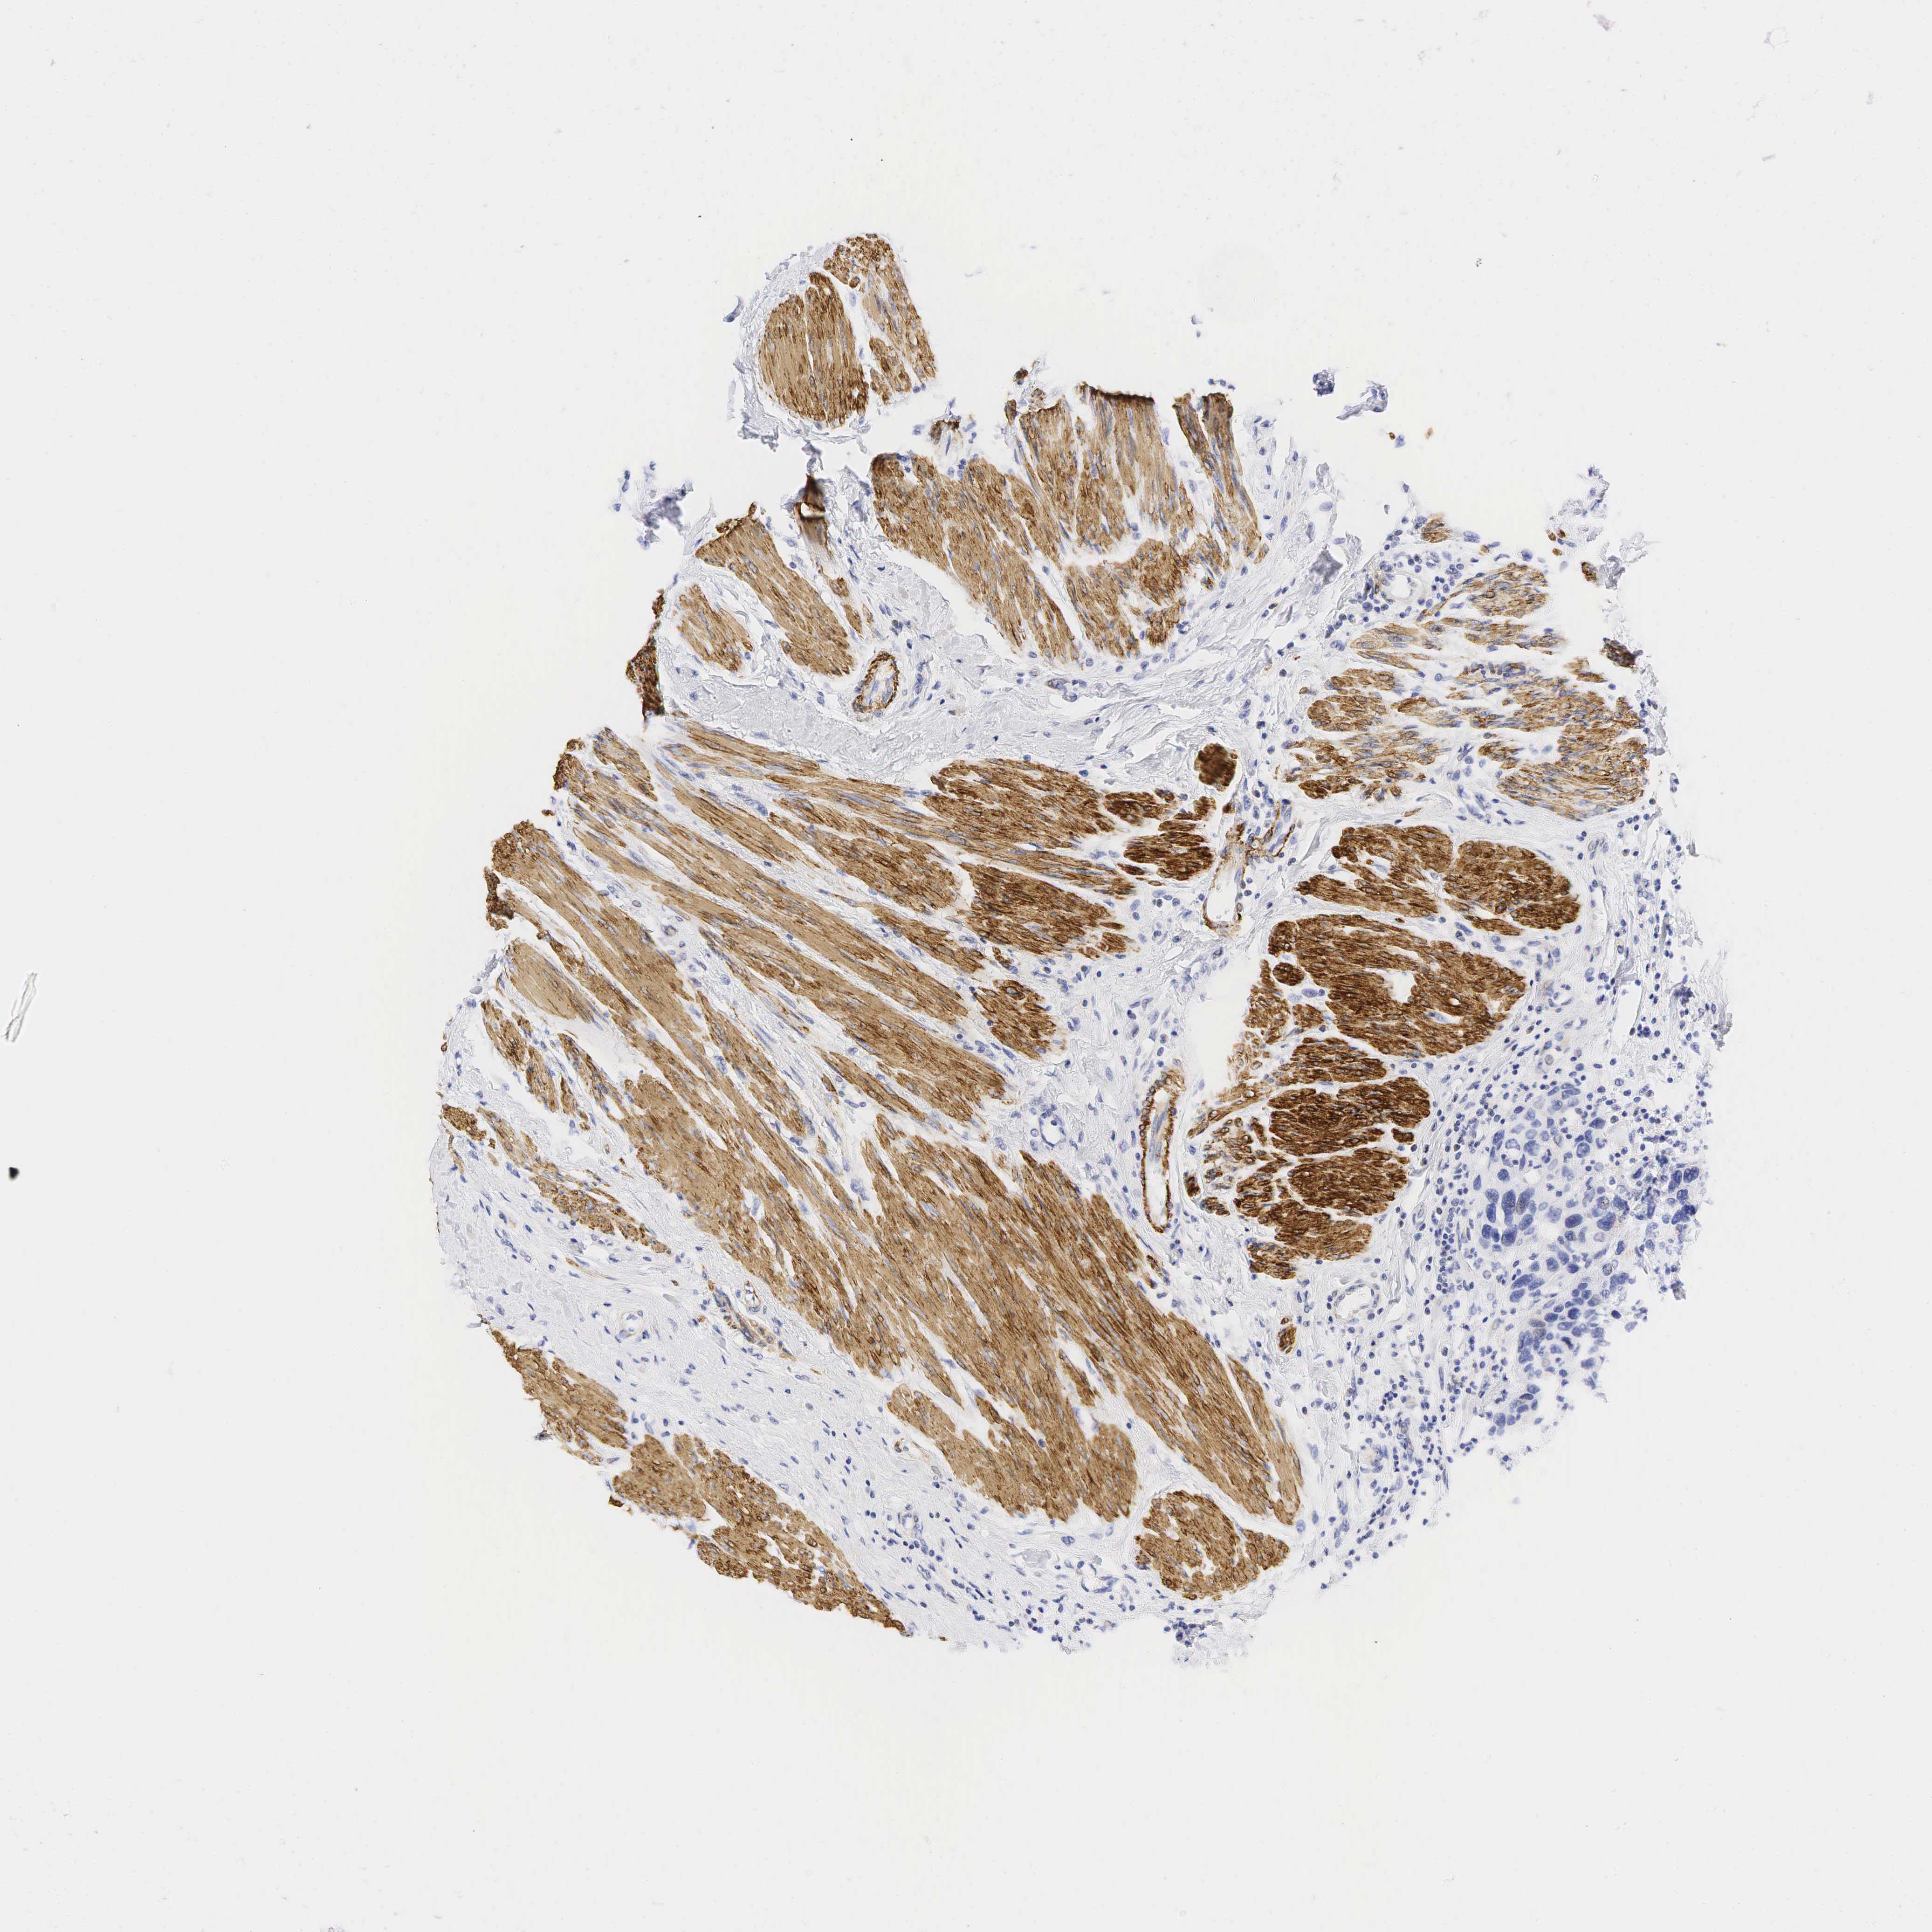

UROTHELIAL CANCER - Protein expressioni

A mouse-over function shows sample information and annotation data. Click on an image to view it in a full screen mode. Samples can be filtered based on level of antibody staining by selecting one or several of the following categories: high, medium, low and not detected. The assay and annotation is described here.

Antibody stainingi

Antibody staining in the annotated cell types in the current human tissue is reported as not detected, low, medium, or high, based on conventional immunohistochemistry profiling in selected tissues. This score is based on the combination of the staining intensity and fraction of stained cells.

Each image is clickable and will lead to virtual microscopy that enables deeper exploration of all samples and also displays staining intensity scores, fraction scores and subcellular localization as well as patient and tissue information for each sample.

Antibody HPA008066

Antibody HPA017330

Antibody CAB000006

Staining

High

Medium

Low

Not detected

Intensity

Strong

Moderate

Weak

Negative

Quantity

>75%

75%-25%

<25%

None

Location

Nuclear

Cytoplasmic/membranous

Cytoplasmic/membranous,nuclear

Urothelial carcinoma, Low grade

Urothelial carcinoma, High grade